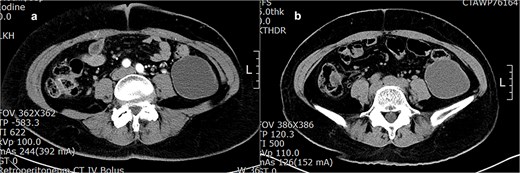

A 50-year-old female patient initially presented 3 years ago with uterine myoma. At that time, retroperitoneal enhanced computed tomography scan revealed multiple uterine myomas and an 8.0 × 5.8 cm lobulated cystic mass with smooth border in the left lower retroperitoneum (Fig. 1a). The cystic mass was suspected to be a retroperitoneal lymphangioma, and since there were no symptoms related to it, the patient decided to undergo observation rather than surgical removal. Since then, size, number, and feature of myomas and retroperitoneal mass showed no change in the follow-up annual CT (Fig. 1b). Recently, although the patient had no specific symptoms related to the cystic tumor, she felt that her abdomen was gradually becoming more bloated. As a result, she opted for surgical removal. The evaluation for serum tumor markers was not conducted. The surgically resected tumor was a large-sized, well-demarcated multilocular cyst with multifocal wall calcification, measuring 142 g and 10.5 × 6.8 × 4.5 cm. There were no ascites, lymphadenopathy, or adhesion to surrounding organs. Both ovaries were normal. The cyst contained clear mucinous fluid and showed focal papillary excrescences, measuring 2.4 × 2.0 cm. Microscopically, the cyst was mainly lined by a single layer of mucin-secreting columnar epithelium (Fig. 2a). In papillary excrescences, papillae lined by stratified mucinous epithelium with moderate nuclear atypia were observed (Fig. 2b). The tumor cells were positive for cytokeratin 7, and negative for cytokeratin 20 and calretinin. Ovarian-like stroma was found and showed positivity for estrogen receptor. No stromal invasion was found. Histologic diagnosis was PRMCTB. During a follow-up period of 24 months, there was no recurrence or metastasis.

(a) Retroperitoneal enhanced CT shows a lobulated homogeneous cyst in the left lower abdomen. (b) A year later, there was no change in the size, shape, or characteristics of the cyst.